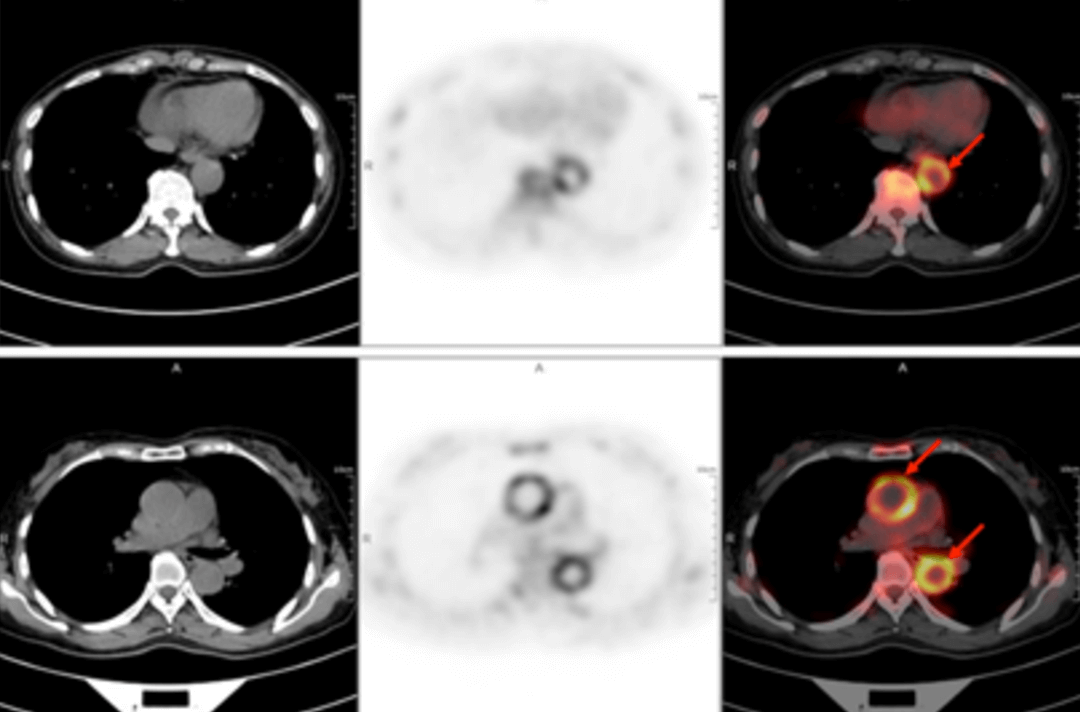

A 58-year-old women went to the hospital for intermittent fever for more than 40 days. Her highest body temperature was 38.9℃. Other symptoms included fatigue and shoulder joint pain which were especially acute in the afternoon and at night without cold, chills, sputum, hemoptysis, chest pain, chest tightness and shortness of breath. After two weeks of intravenous administration of "cephalosporin antibiotics" there was no improvement, and intermittent fever continued. The outpatient clinics noted the patient had "fever of unknown origin." There were no obvious diagnostic features upon physical examination. The results of a routine blood test were as follows: erythrocyte sedimentation rate in the first hour: 72mm; high-sensitivity C-reactive protein: 204. 20mg/l. Then, the patient had a whole-body F-FDG PET-CT examination to find the cause of the fever of unknown origin.

In the PET/CT images, wall thickening with increased glucose metabolism occurred in several parts of the body (bilateral internal carotid artery, common carotid artery, brachiocephalic trunk, bilateral subclavian and axillary arteries, thoracic aorta, abdominal aorta, bilateral common iliac artery, internal iliac artery, external iliac artery and femoral artery), which was considered to be caused by inflammatory changes. Combined with the patient’s medical history, clinical symptoms, examination and imaging findings, she was diagnosed with T.A. After standardized anti-inflammation treatment, her body temperature dropped and her condition improved.